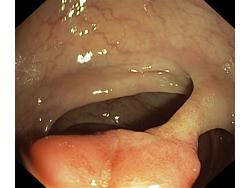

Polipy